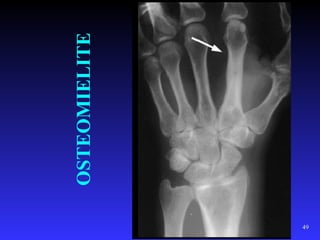

OSTEOMIELITE